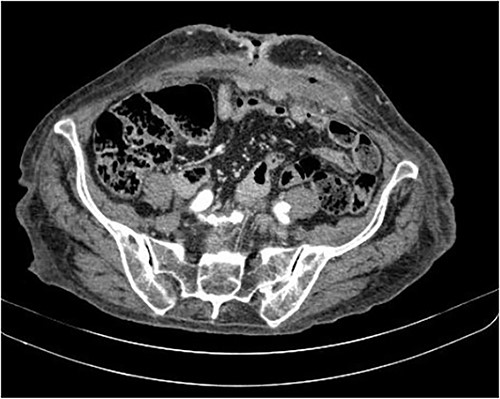

The axial CT section of the abdomen shows the loops in contact with the anterior abdominal wall at the level of the scar umbilical cord. The collection decreased compared with the previous CT scan in the subcutaneous tissue of the umbilical region.